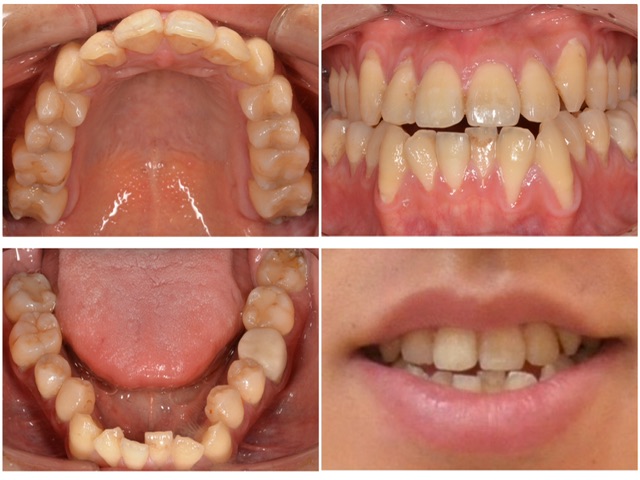

歯並びを治したい 20代男性 2024.9.2

主訴・術前 歯並びを治したい 術後の患者様の感想 院内の清潔感があってとても良かったです。 また、親身で迅速な対応をして下さるのでこちらの要望も伝えやすく、ありがたかったです。 治療情報 主訴 歯並びを治したい 診断名 叢生 年齢 20代男…